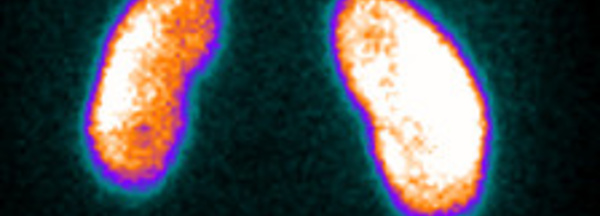

-Détection de séquelles de pyélonéphrite -Diagnostic de pyélonéphrite aiguë -Détection d'anomalies associées : duplicité rénale, petit rein, tissu dysplasique -Détection de rein ectopique...

-Syndrome de la jonction pyélourétérale -Hydronéphrose, urétéro-hydronéphrose, mégauretère. -Dysplasie rénale -Duplicité rénale compliquée -Néphropathie de reflux -Traumatisme rénal -Suspicion...